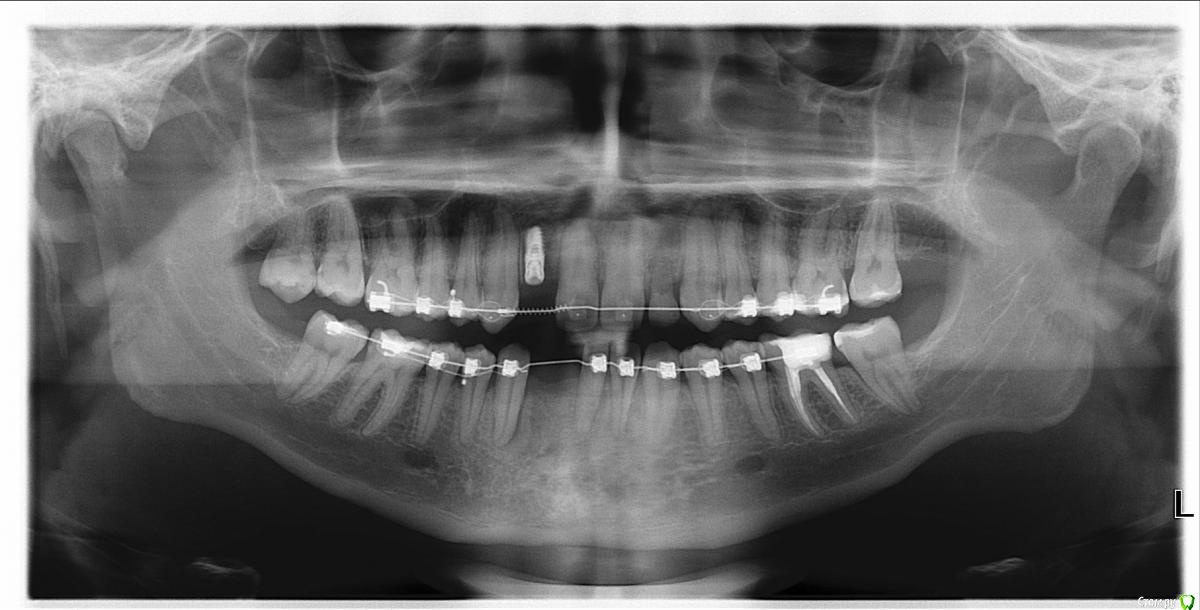

kimon Опубликовано 28 июля, 2016 Поделиться Опубликовано 28 июля, 2016 Здравствуйте, прошу совета. Мне 27 лет, нет двух передних нижних зубов (снимок приложил), нет, потому что просто не выросли коренные зубы. Сейчас занялся зубами, ношу брекеты, дошло дело до имплантации и выяснилось(делали КТ), что в нижней челюсти для двух имплантатов просто не хватает места.Хирург посоветовал поставить 1 имплантат, а соседние зубы увеличить пломбированием. Сказал что вместо 4х передних зубов будет 3 больших. Но там как буд-то слишком большое расстояние и будут щели. Между зубами сейчас щель шириной в 9 мм. Подскажите пожалуйста, есть ли возможность в такой ситуации сделать красиво?Консультировался с ортопедом, но он сказал что на импланте как предлагает хирург красиво точно не получится и предложил сделать мост на зубах. Незнаю что делать, любые деньги готов был отдать чтобы все эстетично получилось.. Ссылка на комментарий

колесников Опубликовано 28 июля, 2016 Поделиться Опубликовано 28 июля, 2016 Мне кажется или центральная линия не совпадает,а 33 на уровне 22? Вы уверены что ортодонтическое лечение завершено? Ссылка на комментарий